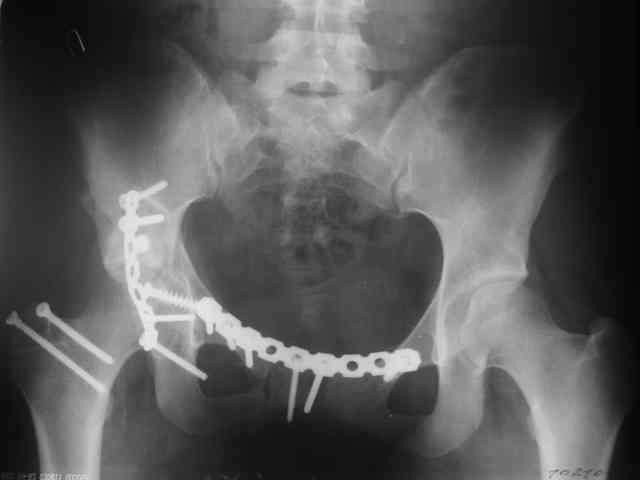

P.S. в приложении R пациентки с похожей проблемой доступа.. за исключением того, что перелом

двухколонный. Вертлугу лечили Y доступом.

Дальше как обычно: рекон пластнина на заднюю колонну. Устранить смещение передней колонны из заднего доступа оказалось невозможным, пришлось

перевернуть больную на спину и из подвздошного доступа вернуть переднюю колонну на место. Другая проблема возникла с фиксацией лонной кости,

пришлось открывать ся над лобком и ретроградно двумя винтами фиксировать обе ветви лобковой кости справа и слева.

Пока всё ОК снимки сделали сегодня, но пока не сфотографировал В целом суставная поверхность конгруэнтна , по колоннам тоже вроде все ОК.

Интраопер под ЭОПом контролировал направление лонного винта - была абсолютная уверенность в правидльности направл, на постоп. снимке винт вылез :-((.